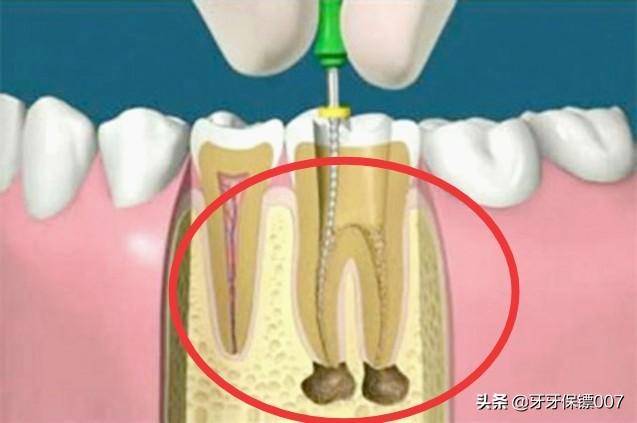

私は何度も何度も医師に確認した後、根管治療を行うことを決めた。 当初、私はまた、百度いくつかの情報を持っている、多くの人々は根管治療を持っていないと言う、良い医者は根管治療に行くことを提案しないのですか?なぜなら、結局のところ、根管治療後の歯は、歯槽を通して栄養を吸収することができないので、歯はますます悪化し、最終的に修復不可能の終わりになるだけです。根管治療はクラウンをかぶせることでもあり、クラウンの値段はもちろんのこと、その派手さとか・・・・・・だから、根管治療を提案してくれた先生のことはそんなに好きではない。

歯髄炎を起こすほど歯髄が傷ついていない場合、一般的に言えば、直接歯を埋めることができます!価格も比較的安く、通常は数種類の材料があり、数百ドルで選ぶことができます!歯髄炎を引き起こすほど歯髄が深い場合は、根管治療を受ける必要があります!根管治療とは簡単に言うと、歯の神経を殺すことで、根管治療が終わると二度と歯が痛くなることはありません!

根管治療の料金は場所によって異なり、歯の根管の数で料金を決めるところもあれば、歯の種類で料金を決めるところもあります!一般的に、大きな歯や切歯は料金が高くなります!根管治療には、1本の歯で1,500ドルから3,000ドルの費用がかかります。根管治療の後は、中の虫歯を取り除かなければならないので、詰め物も必要になります。